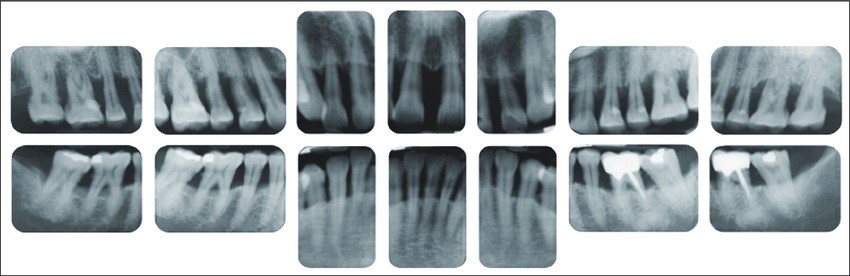

При необходимост от подробна оценка и проследяване на цялостното пародонтално състояние на съзъбието, информация за кариозни лезии, периодонтални заболявания или друга патология в челюстите се правят между 14 и 18 сегментни периапикални зъбни снимки.